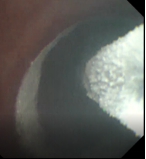

术前支气管 术中改变 术后支气管

接受新疗法的患者两年前就明确诊断为慢阻肺,之后长期吸入大剂量信必可治疗,但咳痰和气急的症状仍控制不佳,本次入院复查发现肺功能明显下降,为中度阻塞性通气功能障碍。4月15日,王昌惠主任、李萍主任医师和李譞主治医师运用冷冻喷雾技术,成功完成COPD患者的支气管粘膜消融手术,术后患者无不良反应发生,第二天即顺利出院。症状得到明显改善,患者对王昌惠教授团队的感激之情溢于言表。

王昌惠教授表示,纤毛功能障碍、黏液高分泌、细菌定植增加、气道炎症与氧化应激等均为慢阻肺发病的重要机制,近几年随着支气管镜介入技术的不断进步, 非药物治疗方式的液氮计量冷冻喷雾成为研究热点。团队的研究和实践均提示,冷冻喷雾消融治疗可以促进支气管粘膜上皮再生,减少杯状细胞的数量,改善纤毛的运动,进而提高COPD患者的生活质量,同时冷冻治疗具有并发症少、恢复快、不易形成瘢痕组织导致气道狭窄等优势,是COPD患者治疗的新希望,也是团队今后继续努力探索的方向。